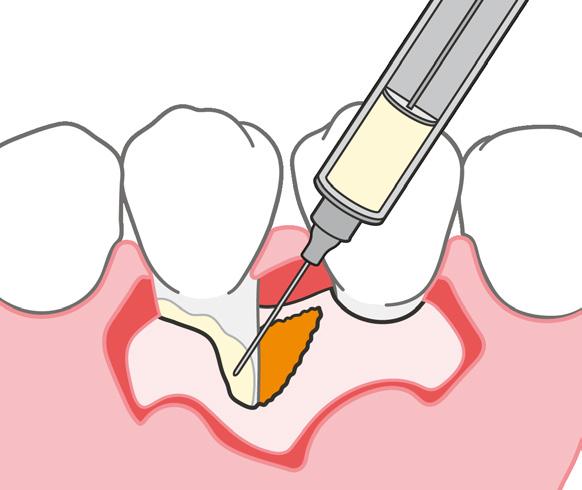

Los dientes anteriores (n.º 13 23) se feru lizaron con una férula periodontal Rib bond, y la oclusión se ajustó a un contac to ligero. Se elevó un colgajo de espesor total, y el defecto se descontaminó con una combinación de láser de CO2 de 9,3 micras y EDTA al 24 %. Después de la descontaminación confirmamos un de fecto de una pared con una bolsa perio dontal intraósea de 7 mm. Injertamos el defecto con Geistlich Bio‑Oss® Collagen, que tiene una excelente capacidad para actuar como andamiaje y resulta muy útil en esta indicación.1 Después cubrimos el injerto óseo con L PRF™ para una mejor respuesta angiogénica de los tejidos.

| A Antes del tratamiento ortodóncico. | B CBCT periapical antes del tratamiento periodontal. | C Dientes (13 y 23) ferulizados. | D Bolsa intraósea de 7 mm después de abrir el colgajo. | E Geistlich Bio-Oss® Collagen rellenando el defecto. | F Membrana L-PRF™ bioactiva cubriendo el injerto óseo. |